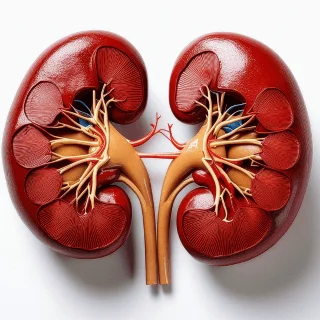

Nefrectomía

Resección parcial o total del riñón, indicada principalmente para el tratamiento del cáncer renal; por lo tanto, es un procedimiento clave en la urología oncológica.